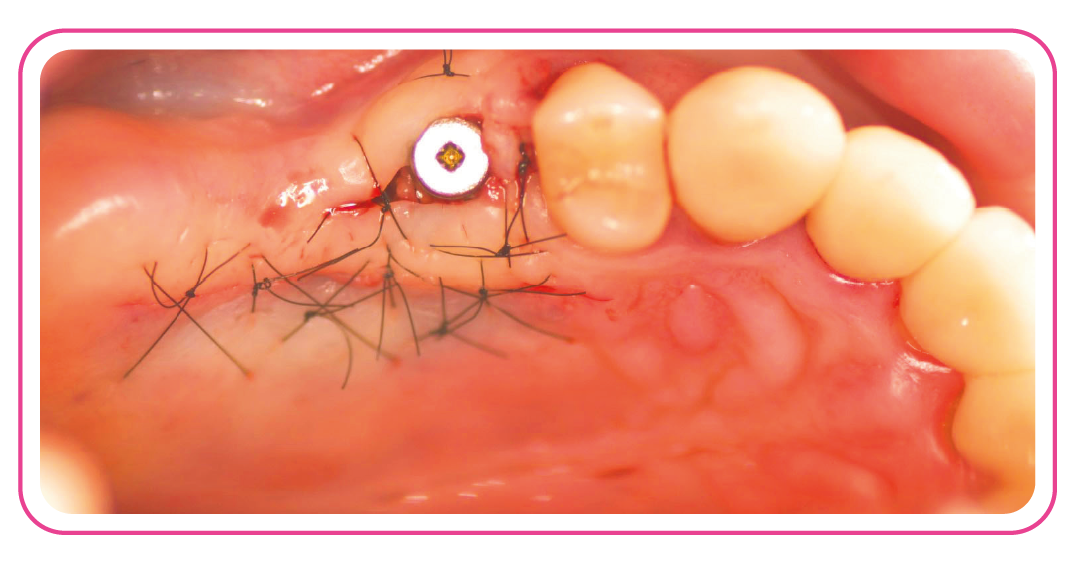

V teoretických i praktických blocích se zaměříme na techniky práce s měkkými tkáněmi, péči po mikrochirurgickém šití, chirurgické postupy a moderní techniky, včetně využití kinesiotapingu. Kurz je určen jak začátečníkům, tak pokročilejším lékařům a bude vedený v anglickém jazyce.

Kurz probíhá během dvou dnů a propojuje teoretické bloky s praktickými cvičeními, které se soustředí na práci s měkkými tkáněmi, mikrochirurgické techniky a řešení komplikací. Součástí je také večerní setkání s lektorem.